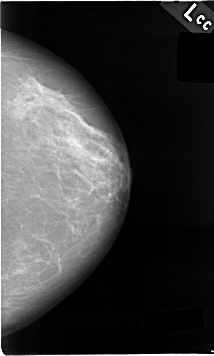

C_0009_1.LEFT_CC

LEFT_CC LINES 4624 PIXELS_PER_LINE 2776 BITS_PER_PIXEL 12 RESOLUTION 50 NON_OVERLAY